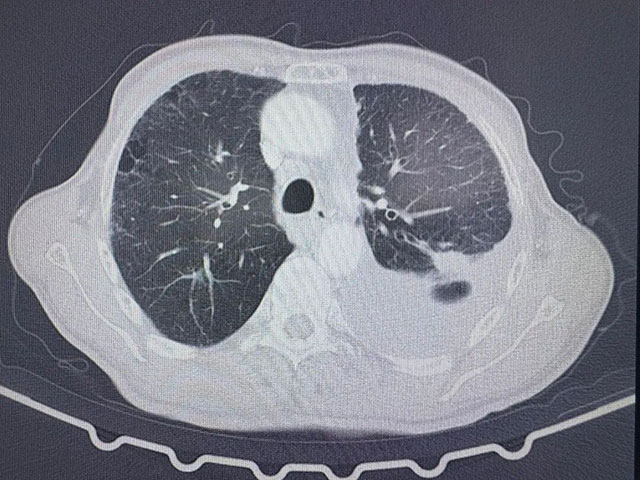

术前胸部CT

入院时,张爷爷的病情已十分危急,胸心外科副主任刘浩副教授检查发现:左肺存在恶性结节,左侧胸腔中量积液,肺部感染严重。